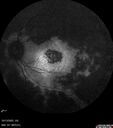

Elmiron (pentasosan polysulfate) Macular Toxicity104 views77 year old female who had been on Elmiron for 20 years and stopped it 2 years agoMar 15, 2026

Elmiron (pentasosan polysulfate) Macular Toxicity89 views77 year old female who had been on Elmiron for 20 years and stopped it 2 years agoMar 15, 2026

Elmiron (pentasosan polysulfate) Macular Toxicity35 views77 year old female who had been on Elmiron for 20 years and stopped it 2 years agoMar 15, 2026

Elmiron (pentasosan polysulfate) Macular Toxicity41 views77 year old female who had been on Elmiron for 20 years and stopped it 2 years agoMar 15, 2026

Elmiron (pentasosan polysulfate) Macular Toxicity45 views77 year old female who had been on Elmiron for 20 years and stopped it 2 years agoMar 15, 2026

Elmiron (pentasosan polysulfate) Macular Toxicity46 views77 year old female who had been on Elmiron for 20 years and stopped it 2 years agoMar 15, 2026

Elmiron (pentasosan polysulfate) Macular Toxicity38 views77 year old female who had been on Elmiron for 20 years and stopped it 2 years agoMar 15, 2026

Elmiron (pentasosan polysulfate) Macular Toxicity37 views77 year old female who had been on Elmiron for 20 years and stopped it 2 years agoMar 15, 2026

Elmiron (pentasosan polysulfate) Macular Toxicity36 views77 year old female who had been on Elmiron for 20 years and stopped it 2 years agoMar 15, 2026

Elmiron (pentasosan polysulfate) Macular Toxicity40 views77 year old female who had been on Elmiron for 20 years and stopped it 2 years agoMar 15, 2026